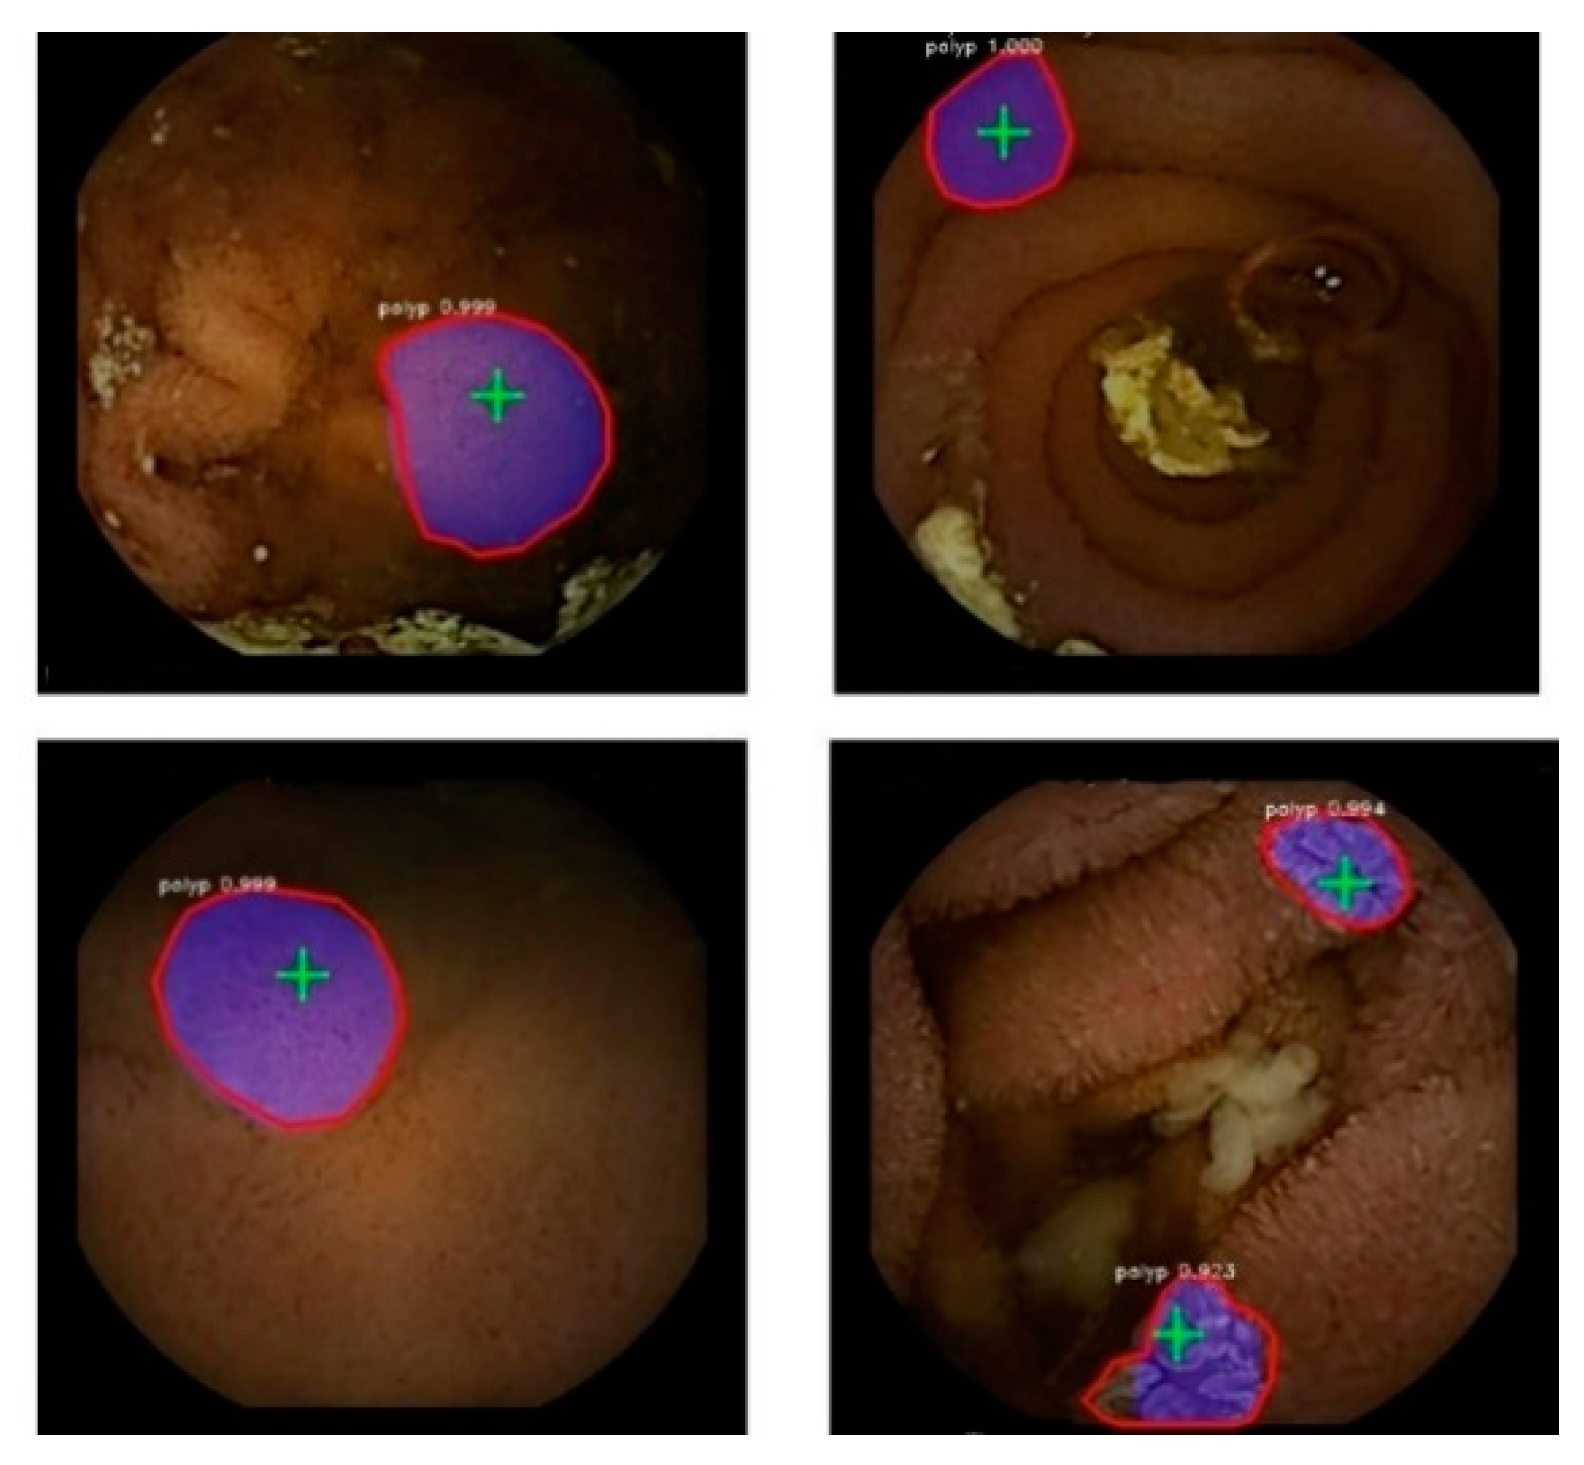

Figure 6 displays the detection and segmentation results on the WCE polyp test data based on the proposed approach with ResNet-101 and Flickr’s balloon data.

Figure 6.

Polyp segmentation in WCE video frames. Blue overlay indicates the predicted segmentation mask. The contour of the ground truth masks is shown in red. Detection points are masked in green.